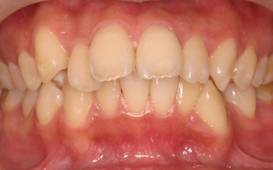

インビザラインによる矯正症例2 22歳女性

治療開始時。正中離開と過蓋咬合がありました

治療途中 5か月後

治療終了 治療開始後7か月